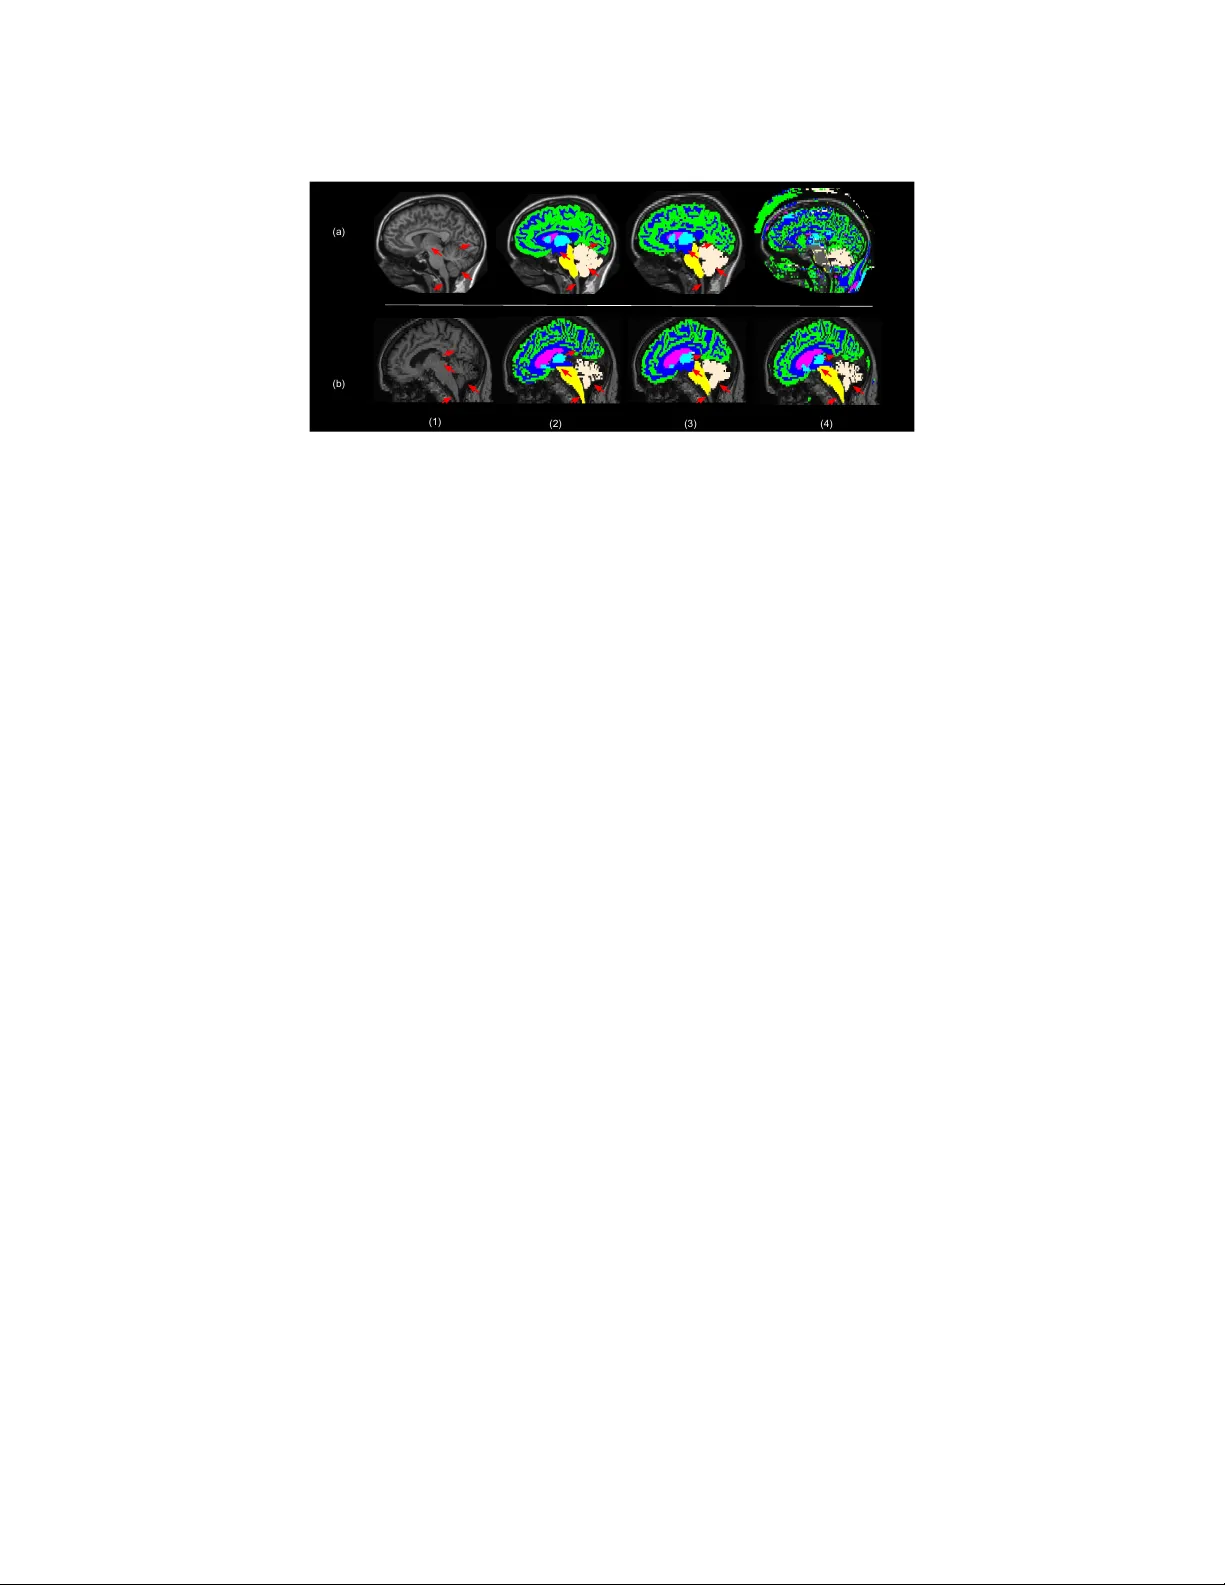

1 – 11 MIDL 2019 – F ull paper track Learning join t lesion and tissue segmen tation from task-sp ecific hetero-mo dal datasets Reub en Doren t 1 reuben.dorent@kcl.a c.uk W enqi Li 1 wenqi.li@kcl.a c.uk Jinendra Ek anay ake 2 j.ekana y ake@ucl.ac.uk Sebastien Ourselin 1 sebastien.ourselin@kcl.a c.uk T om V ercauteren 1 tom.verca uteren@kcl.a c.uk 1 Scho ol of Biome dic al Engine ering & Imaging Scienc es, Kings Col le ge L ondon, L ondon, UK 2 Wel lc ome / EPSRC Centr e for Interventional and Sur gic al Scienc es, UCL, L ondon, UK Abstract Brain tissue segmentation from m ultimo dal MRI is a key building blo c k of many neuro- science analysis pip elines. It could also play an important role in man y clinical imaging scenarios. Established tissue segmentation approaches hav e how ever not b een developed to cop e with large anatomical changes resulting from pathology . The effect of the pres- ence of brain lesions, for example, on their performance is th us curren tly uncon trolled and practically unpredictable. Contrastingly , with the adven t of deep neural netw orks (DNNs), segmen tation of brain lesions has matured significantly and is achieving p erformance levels making it of interest for clinical use. Ho wev er, few existing approaches allow for jointly segmen ting normal tissue and brain lesions. Dev eloping a DNN for suc h joint task is cur- ren tly hamp ered by the fact that annotated datasets typically address only one sp ecific task and rely on a task-specific hetero-mo dal imaging proto col. In this work, w e propose a no vel approach to build a join t tissue and lesion segmentation mo del from task-specific hetero-mo dal and partially annotated datasets. Starting from a v ariational formulation of the joint problem, we show how the exp ected risk can b e decomp osed and optimised empirically . W e exploit an upper-b ound of the risk to deal with missing imaging modali- ties. F or eac h task, our approac h reac hes comparable performance than task-sp ecific and fully-sup ervised mo dels. Keyw ords: join t learning, lesion segmen tation, tissue segmen tation, hetero-mo dalit y , w eakly-sup ervision 1. In tro duction T raditional approac hes for tissue segmentation used in brain segmen tation softw are pack ages suc h as FSL ( Jenkinson et al. , 2012 ), SPM ( Ashburner and F riston , 2000 ) or NiftySeg ( Cardoso et al. , 2015 ) are based on sub ject-sp ecific optimisation. FSL and SPM fit a Gaussian Mixture Model to the MR in tensities using either a Mark o v Random Field (MRF) or tissue prior probability maps as regularisation. Alternativ ely , multi-atlas metho ds rely on lab el propagation and fusion from m ultiple fully-annotated images, i.e. atlases, to the target image ( Iglesias and Sabuncu , 2015 ). These metho ds t ypically require extensiv e pre- pro cessing, e.g. skull stripping, correction of bias field or registration. They are also often time-consuming, and are inherently only adapted for brains devoid of large anatomical c  R.D. , W.L. , J.E. , S.O. & T.V. . c hanges induced b y pathology . Indeed, it has been sho wed that the presence of lesions distorts the registration output ( Sdik a and Pelletier , 2009 ). Similarly , lesions introduce a bias in the MRF. This leads to a p erformance degradation in presence of lesions for brain v olumes measuremen t ( Battaglini et al. , 2012 ) and any subsequent analysis. While quan titativ e analysis is expected to pla y a k ey role in impro ving the diagnosis and follo w-up ev aluations of patien ts with brain lesions, current to ols mostly focus on the lesions themselv es. Existing quantitativ e neuroimaging approac hes allow the extraction of imaging biomark ers suc h as the largest diameter, volume, and coun t of the lesions. Thus, automatic segmen tation of the lesions promises to speed up and impro ve the clinical decision-making pro cess but more refined analysis would b e feasible from tissue classification and region parcellation. As such, although very few w orks ha ve addressed this problem y et, a join t mo del for lesion and tissue segmentation is expected to bring significant clinical impact. Deep Neural Net works (DNNs) b ecame the state-of-the-art for most of the segmen tation tasks and one w ould now expect to train a joint lesion and tissue segmen tation algorithm. Y et, DNNs require a large amount of annotated data to b e successful. Existing annotated databases are usually task-sp ecific, i.e. pro viding either scans with brain tissue annotations for patients/con trols dev oid of large pathology-induced anatomical changes, or lesion scans with only lesion annotations. F or this reason, the imaging protocol used for the acquisition also typically differs from one dataset to another. Indeed, tissue segmen tation is usually p erformed on T1 scans, unlike lesion segmen tation which normally also encompasses Flair ( Barkhof and Scheltens , 2002 ). Similarly , the resolution and contrast among databases ma y also v ary . Given the large amoun t of resources, time and exp ertise required to annotate medical images, given the v arying imaging requirement to supp ort each individual task and giv en the a v ailability of task-specific databases, it is unlikely that large databases for every join t problem, such as lesion and tissue segmen tation, will b ecome av ailable for researc h purp oses. There is th us a need to exploit task-sp ecific databases to address joint problems. Learning a join t mo del from task-specific hetero-modal datasets is nonetheless c hallenging. This problems lies at the in tersection of Multi-T ask Learning, Domain Adaptation and W eakly Sup ervised Learning with idiosyncrasies making individual metho ds from these underpinning fields insufficient to address it completely . Multi-T ask Learning (MTL) aims to p erform several tasks simultaneously b y extracting some form of common knowledge or represen tation and introducing a task-sp ecific back- end. When relying on DNN for MTL, usually the first la y ers of the net work are shared, while the top lay ers are task-sp ecific. The global loss function is often a sum of task-sp ecific loss functions with manually tuned w eigh ts. Recently , Kendall and Gal ( 2017 ) prop osed a Bay esian parameter-free metho d to estimate the MTL loss w eights and Bragman et al. ( 2018 ) extended it to spatially adaptiv e task w eighting and applied it to medical imaging. In addition to arguably subtle differences betw een MTL and join t learning discussed in more depth later, MTL approaches do not pro vide any mechanism for dealing with hetero-mo dal datasets and changes in imaging c haracteristics across task-sp ecific databases. Domain Adaptation (D A) is a solution for dealing with heterogeneous datasets. The main idea is to create a common feature space for the t wo sets of scans. Csurk a ( 2017 ) prop osed an extensiv e comparison of these methods in deep learning. Learning from hetero- mo dal datasets could b e consider as a particular case of D A. Ha v aei et al. ( 2016 ) prop osed a netw ork arc hitecture for dealing with missing mo dalities. How ever, DA metho ds fo cus 2 Joint lesion and tissue segment a tion from t ask-specific heter o-modal d a t asets on solving a single task and rely on either fully-sup ervised approaches or unsup ervised adaptation as done b y Kamnitsas et al. ( 2017 ). W eakly-sup ervised Learning (WSL) deals with missing, inaccurate, or inexact annota- tions. Our problem is a particular case of learning with missing lab els since each dataset pro vide a set of lab els and the tw o sets are disjoin t. Li and Hoiem ( 2017 ) proposed a metho d to learn a new task from a mo del trained on another task. This metho d com bines D A through transfer learning and MTL. At the end, tw o mo dels are created: one for the first task and one for the second one. Kim et al. ( 2018 ) extent this approach by using a kno wledge distillation loss in order to create a unique joint mo del. This aims to alternativ ely learn one task without forgetting the other one. The WSL problem w as th us decomposed in to a MTL problem with similar limitations for our sp ecific use case. The con tributions of this work are four-fold. First w e prop ose a joint mo del that p er- forms tissue and lesion segmentation as a unique joint task and thus exploits the in terdep en- dence betw een lesion and tissue segmentation tasks. Starting from a v ariational form ulation of the joint problem, w e exploit the disjointness of the lab el sets to prop ose a practical decomp osition of the joint loss. Secondly , w e in tro duce feature channel a veraging across mo dalities to adapt existing net works for our hetero-mo dal problem. Thirdly , we develop a new metho d to minimise the exp ected risk under the constrain t of missing mo dalities. Relying on reasonable assumptions, we sho w that the expected risk can b e further decom- p osed and minimised via a tractable upp er b ound. T o our kno wledge, no suc h optimisation metho d for missing mo dalities in deep learning has b een published b efore. Finally , we ev al- uate our framework for white matter lesions and tissue segmentation. W e demonstrate that our joint approac h can achiev e, for eac h individual task, similar p erformance compared to a task-sp ecific baseline. Albeit relying on different annotation proto cols, results using a small fully-annotated join t dataset demonstrate efficient generalisabilit y . 2. Tissue and lesion segmentation as a single task In order to develop a join t mo del, we propose a mathematical v ariational formulation of the problem and a metho d to optimise it empirically . 2.1. F ormal problem statemen t Let x = ( x 1 , .., x M ) ∈ X = R N × M b e a v ectorized multimodal image and y ∈ Y = { 0 , .., C } N its asso ciated segmen tation map. N , M and C are resp ectiv ely the n umber of vo xels, mo dalities and classes. Our goal is to determine a predictive function h θ : X 7→ Y that minimises the discrepancy b et ween the ground truth label v ector y and the prediction h θ ( x ). Let L b e a loss function that computes this discrepancy . F ollowing the formalism used by Bottou et al. ( 2018 ), giv en a probability distribution D ov er ( X , Y ) and random v ariables ( X , Y ) under this distribution, we wan t to find θ ∗ suc h that: θ ∗ = argmin θ E ( X,Y ) ∼D [ L ( h θ ( X ) , Y )] (1) Let C t , C l and 0 b e resp ectively the tissue classes, the lesion classes and the background class. Since C t and C l are disjoint, the segmentation map y can b e decomp osed into tw o segmen tation maps y i = y l i + y t i with y t i ∈ C t ∪ { 0 } , y l i ∈ C l ∪ { 0 } , as shown in Figure 1 . 3 Figure 1: Decomp osition of the label map in to the sum of t wo segmentation maps. Let’s assume that the loss function L can also b e decomp osed into a tissue loss function L t and a lesion loss function L l . This is common for multi-class segmen tation loss functions in particular for those with one-versus-al l strategies (e.g. Dice loss, Jaccard loss): L ( h θ ( X ) , Y ) = L t ( h θ ( X ) , Y t ) + L l ( h θ ( X ) , Y l ) ( H 1 ) Then, Equation ( 1 ) can be rewritten as: θ ∗ = argmin θ E ( X,Y ) ∼D [ L t ( h θ ( X ) , Y t )] | {z } R t ( θ ) + E ( X,Y ) ∼D [ L l ( h θ ( X ) , Y l )] | {z } R l ( θ ) (2) 2.2. On the distribution D in the context of heterogeneous databases As we exp ect different distributions across heterogeneous databases, t wo probability distri- butions of ( X , Y ) o ver ( X , Y ) can b e distinguished: 1/ under D control , ( X, Y ) corresp onds to a multimodal scan and segmentation map of a patient without lesions. Note that although w e use the term c ontr ol for con venience, w e exp ect to observ e pathology with ”diffuse” anatomical impact, e.g. from dementia. 2/ under D lesion , ( X , Y ) corresp onds to a multi- mo dal scan and segmen tation map of a patien t with lesions. Since traditional methods are not adapted in the presence of lesions, the most important and challenging distribution D to address is the one for patients with lesions, D lesion . In the remainder of this w ork w e th us assume that: D , D lesion . ( H 2 ) 2.3. Hetero-mo dal net work arc hitecture In order to learn from hetero-mo dal datasets, w e need a net work arc hitecture that allo ws for missing mo dalities. W e prop osed an architecture inspired by HeMIS ( Hav aei et al. , 2016 ) and HighResNet ( Li et al. , 2017 ) shown in Figure 2 . F eatures of each mo dalit y are first extracted separately and are then a v eraged. The spatial resolution of the input and the output are the same. Dilated conv olutions and residual connections are used to capture information at multiple scales and a void the problem of v anishing gradien ts. This netw ork with w eigh ts θ is used to capture the predictiv e function h θ . 4 Joint lesion and tissue segment a tion from t ask-specific heter o-modal d a t asets μ 3x3x3 convolutions 8 Kernels Batch Norm. ReLU 3x3x3 convolutions 16 kernels, dilated by 2 Batch Norm. ReLU 3x3x3 convolutions 16 kernels, dilated by 4 Batch Norm. ReLU 3x3x3 convolutions 8 Kernels 1x1x1 convolutions 32 Kernels ReLU ReLU 1x1x1 convolutions |C| Kernels ReLU Block with residual connections μ Mean T1 Flair Figure 2: The prop osed net w ork architecture: a mix b et ween HighResNet and HeMIS. T o a void cluttering, only one of the three con volution blo c ks is shown in the residual blo c ks. 2.4. Upp er-b ound for the tissue exp ected risk R t Although thanks to its hetero-mo dal architecture, h θ ma y now handle inputs with v arying n umber of mo dalities, the curren t decomp osition of ( 1 ) assumes that all the mo dalities of X are a v ailable for ev aluating the loss. In our scenario, w e ha ve only access to T1 con trol scans with tissue annotations or T1 and Flair scans with only lesion annotations. Consequently , as w e do not hav e an y T1 and Flair images with tissue annotations, and as ev aluating a loss with missing mo dalities would lead to a bias, estimating R t is not straightforw ard. In this section w e prop ose an upp er-bound of R t using T1 control images with tissue annotations and outputs from the net w ork. Let’s assume that the loss function L t satisfies the triangle inequality (e.g. Jaccard loss): ∀ ( a, b, c ) ∈ Y 3 : L t ( a, c ) ≤ L t ( a, b ) + L t ( b, c ) ( H 3 ) Let p denote the pro jection of x (will all the modalities) to the T1 mo dality , p : x = ( x T1 , x Flair ) 7→ x T1 . Under ( H 3 ), L t satisfies the following inequality: L t ( h θ ( X ) , Y t ) ≤ L t ( h θ ( X ) , h θ ( p ( X ))) + L t ( h θ ( p ( X )) , Y t ) (3) In com bination with ( H 2 ), this leads to: R t ( θ ) ≤ E ( X,Y ) ∼D lesion [ L t ( h θ ( X ) , h θ ( p ( X )))] + E ( X,Y ) ∼D lesion [ L t ( h θ ( p ( X )) , Y t )] (4) The decomp osition in ( 4 ) requires comparison of inference done from T1 inputs, i.e. h θ ( p ( X )) with ground truth tissue maps Y t . While this pro vides a step tow ards a practical ev aluation of R t , we still face the c hallenge of not ha ving tissue annotations Y t under D lesion . Let us further assume that the restriction of the distributions D lesion and D control to the parts of the brain not affected by lesions are the same, i.e.: ∀ i ∈ { 1 ...N } P D lesion ( x i , y i | y i ∈ C tissue ) = P D control ( x i , y i | y i ∈ C tissue ) ( H 4 ) 5 By com bining ( H 3 ) and ( H 4 ), an upp er bound of R t can be provided as: R t ( θ ) ≤ E ( X,Y ) ∼D lesion [ L t ( h θ ( X ) , h θ ( p ( X )))] | {z } R t 1 ( θ ) + E ( X,Y ) ∼D control [ L t ( h θ ( p ( X )) , Y t )] | {z } R t 2 ( θ ) (5) As observed in ( 5 ), the upp er-b ound is the sum of the exp ected loss betw een the T1 scan outputs and the lab els and the exp ected loss b et ween the outputs using either one or tw o mo dalities as input. W e emphasise that, to the b est of our knowledge, this second loss term do es not app ear in existing heteromodal approaches such as HeMIS ( Hav aei et al. , 2016 ). 2.5. Empirical estimation of the decomp osed loss Neural Network T issue segmentation map T umor segmentation map T1 Neural Network Neural Network Control scans Lesion scans Flair Label Label T1 Figure 3: Pro cedure for estimating the ex- p ected risks R l , R t 1 and R t 2 . As is the norm in data-driven learning, w e do not hav e access to the true joint prob- abilities D control or D lesion . The common metho d is to estimate the exp ected risk us- ing training samples. In our case, w e hav e t wo hetero-mo dal training samples S control and S lesion with resp ectively tissue and le- sion annotations. W e can estimate the ex- p ected risks R l ( θ ), R t 1 ( θ ), R t 2 ( θ ) by resp ec- tiv ely using lesion segmentation outputs of lesion T1+Flair scans, tissue segmentation outputs from T1 and T1+Flair scans and tissue segmen tation outputs of con trol T1 scans. Figure 3 illustrates the complete training procedure. 3. Experiments While focusing on the white matter lesion and tissue segmentation problem, our goal in the following experiments is to predict six tissue classes (white matter, gra y matter, basal ganglia, v en tricles, cereb ellum, brainstem), the white matter lesions and the background. 3.1. Data T o demonstrate the feasibility of our join t learning approach, we used three sets of data. Lesion data S lesion : The White Matter Hyp erintensities (WMH) database consists of 60 sets of brain MR images (T1 and Flair, M = 2) with manual annotations of WMH ( http://wmh.isi.uu.nl/ ). The data comes from three differen t institutes. Tissue data S control : Neuromorphometrics provided 32 T1 scans ( M 0 = 1) for MICCAI 2012 with manual annotations of 155 structures of the brain from which we deduct the six tissue classes. In order to hav e balance training datasets for the tw o t yp es of segmentation, and similar to Li et al. ( 2017 ), we added 28 T1 control scans from the ADNI2 dataset with bronze standard parcellation of the brain structures computed with the accurate but time-consuming algorithm of Cardoso et al. ( 2015 ). 6 Joint lesion and tissue segment a tion from t ask-specific heter o-modal d a t asets F ully annotated data: MRBrainS18 ( http://mrbrains18.isi.uu.nl/ ) is composed of 30 sets of brain MR images with tissue and lesions manual annotations. Only 7 MR images are publicly av ailable. W e used this data only for ev aluation and not for training. T o b e consisten t with the lesion data, the cerebrospinal fluid is considered as bac kground. T o satisfy the assumption ( H 4 ), we resampled the data to 1 × 1 × 3 mm 3 , used a histogram-based scale ( Milletari et al. , 2016 ) and a zero-mean unit-v ariance normalization. 3.2. Choice of the loss W e used the probabilistic v ersion of the Jaccard loss for L : L ( h θ ( x ) , y ) = 1 − X c ∈ C ω c P N j =1 g j,c p j,c P N j =1 g 2 j,c + p 2 j,c − g j,c p j,c suc h as X c ∈ C ω c = 1 (6) ( H 1 ) is satisfied b ecause of the one-versus-al l strategy , i.e. sum o ver the classes of a class- sp ecific loss. In order to give the same w eight to the lesion segmen tation and the tissue segmen tation, we choose for an y tissue class c , w c = 1 16 and for the lesion class l , w l = 1 2 . While the triangle inequalit y holds for the Jaccard distance ( Kosub , 2018 ), the pro of that its probabilistic version also satisfies it, i.e. ( H 3 ), is left for future work. 3.3. Implemen tation details W e implemen ted our netw ork in NiftyNet, a T ensorflo w-based open-source platform for deep learning in medical imaging ( Gibson et al. , 2018 ). Con volutional lay ers are initialised such as He et al. ( 2015 ). The scaling and shifting parameters in the batc h normalisation la yers w ere initialised to 1 and 0 respectively . As suggested b y ( Ulyano v et al. , 2016 ), we used instance normalization for inference. W e used the Adam optimisation method ( Kingma and Ba , 2014 ). The learning rate l R , β 1 , β 2 w ere resp ectiv ely set up to 0.005, 0.9 and 0.999. A t each training iteration, we feed the net work with one image from the tissue dataset and one from the lesion dataset. 120 × 120 × 40 sub-v olumes w ere randomly sampled from the training data using an uniform sampling for the tissue data and a weigh ted sampling based on dilated lesions maps for the lesion data. The mo dels w ere trained un til we observ ed a plateau in p erformance on the v alidation set. W e exp erimentally found that the in ter- mo dalit y loss has to be skipp ed for the first (5000) iterations. W e randomly spitted the data in to 70% for training, 10% for v alidation and 20% for testing for each of the 4 folds. 3.4. Results for the joint learning mo del Join t learning versus single task learning First, we compare individual models to the join t mo del using our approach. The lesion segmen tation ( W ) mo del was trained on WMH dataset with the lesion annotations, the tissue segmentation ( N ) on Neuromorphometrics dataset with the tissue annotations, and our metho d ( W+N ) on WMH and Neuromor- phometric datasets with their resp ectiv e set of annotations. The similarit y b et ween the prediction and the ground truth is computed using the Dice Similarit y Co efficien t (DSC) for each class. T able 1 and Figure 4 show the results of these mo dels on test images. The join t mo del and single task mo dels achiev e comparable performance. This suggest that 7 (1) (2) (3) (4) (b) (a) (5) Figure 4: Segmen tation results using our metho d and task-sp ecific models. (1) axial slice from test image v olumes from (a) WMH and (b) Neuromorphometrics, (2) man ual annotations, (3) outputs from the joint learning mo del, (4) outputs from the tissue segmen tation ( N ) model, (5) outputs from the lesion segmentation ( W ) model learning from hetero-mo dal datasets via our metho d do es not degrade the task-sp ecific p er- formance. Moreo ver, we observ e in Figure 4 that the tissue knowledge learn t from T1 scans has been well generalised to multi-modal scans. T able 1: Comparison b etw een the lesion segmen tation mo del W , the tissue segmen tation mo del N , the fully-sup ervised mo del ( M ), a traditional approac h ( SPM ) and our join t mo del ( W+N ). Dice Similarit y Coefficients (%) has been computed. Neuromorphometrics WMH MRBrainS18 N M W+N W M W+N SPM M W+N Gra y matter 88.5 42.0 89.4 76.5 83.3 79.4 White matter 92.4 56.7 92.8 75.7 85.9 85.4 Brainstem 93.4 20.0 93.1 76.5 92.3 72.3 Basal ganglia 86.7 41.2 87.2 74.7 79.1 75.3 V entricles 90.7 24.5 91.6 80.9 91.0 91.7 Cereb ellum 92.5 43.7 94.9 89.4 91.8 90.8 White matter lesion 61.9 50.6 59.9 40.8 53.5 53.7 Join t mo del versus fully-sup ervised mo del In this section, we compare our method ( W+N ) to the fully-supervised ( M ) mo del trained on MRBrainS18 using b oth tissue and lesion annotations. W e ev aluated the p erformance on the three datasets. On the one hand, w e submitted our mo dels to the online challenge MRBrainS18. One of the ma jor b enefits of ev aluating our metho d on a challenge is to directly b enc hmark our metho d with exist- ing methods, in particular with traditional metho ds suc h as SPM ( Ash burner and F riston , 8 Joint lesion and tissue segment a tion from t ask-specific heter o-modal d a t asets (1) (2) (3) (4) (b) (a) Figure 5: Annotation proto col comparison b et ween scans from (a) Neuromorphometrics and (b) MRBrainS18. (1) sagital slice from test images v olumes, (2) man ual an- notations, (3) outputs from our method (W+N) , (4) outputs from fully-supervised mo del (N) . Arro ws sho w the protocol differences. 2000 ). On the other hand, we compared the p erformance on the tissue and lesion datasets using either all the scans ( M ) or the testing split ( W+N ). The DSC was computed for eac h class and T able 1 show the results. First our mo del outp erforms SPM on 6 of the 7 classes. Secondly , the tw o mo dels ac hieve very similar performance on lesion segmen tation. Concerning the tissue segmentation, as exp ected, eac h of the netw ork outp erforms on its training datasets. How ever, the fully sup ervised mo del do esn’t generalise to Neuromorpho- metrics dataset. In con trast, the differences are smaller for the tissue segmentation classes on MRBrainS18. Esp ecially , Figure 5 shows differences in the annotation proto col b et ween MRBrainS18 and Neuromorphometrics for the white matter, brainstem and cerebellum and ho w it affects the predictions. 4. Conclusion W e prop ose a join t mo del learned from hetero-mo dal datasets with disjoint heterogeneous annotations. Our approac h is mathematically grounded, conceptually simple, new and relies on reasonable assumptions. W e v alidated our approac h by comparing our join t model with single-task learning mo dels. W e sho w that similar p erformance can be ac hieved for the tissue segmen tation and lesion segmen tation in comparison to task-sp ecific baselines. Moreov er, our mo del ac hiev es comparable p erformance to a mo del trained on a small fully-annotated join t dataset. Our work shows that the knowledge learn t from one mo dalit y is preserved when more mo dalities are used as input. In the future, we will ev aluate our approach on datasets with annotations proto cols showing less v ariability . F urthermore, exploitation of recen t techniques for domain adaptation could help us bridge the gap and improv e the p erformance by helping to b etter satisfy some of our assumptions. Finally , w e plan to in tegrate uncertaint y measures in our framew ork as a future w ork. As one of the first w ork to methodologically address the problem of join t learning from hetero-mo dal datasets, w e b eliev e that our approac h will help DNN make further impact in clinical scenarios. 9 Ac kno wledgments This work was supp orted by the W ellcome T rust [203148/Z/16/Z] and the Engineering and Physical Sciences Researc h Council (EPSRC) [NS/A000049/1]. TV is supp orted b y a Medtronic / Roy al Academ y of Engineering Research Chair [ RC S R F 1819 \ 7 \ 34]. References John Ashburner and Karl J. F riston. V oxel-based morphometry – the methods. Neur oimage , 11(6):805–821, 2000. F rederik Barkhof and Philip Sc heltens. Imaging of white matter lesions. Cer ebr ovascular Dise ases , 13(Suppl 2):21–30, 2002. Marco Battaglini, Mark Jenkinson, and Nicola De Stefano. Ev aluating and reducing the impact of white matter lesions on brain v olume measurements. Human Br ain Mapping , 33(9):2062–2071, 2012. L ´ eon Bottou, F rank E. Curtis, and Jorge No cedal. Optimization metho ds for large-scale mac hine learning. SIAM R eview , 60(2):223–311, 2018. F elix J. S. Bragman, Ryutaro T anno, Zach Eaton-Rosen, W enqi Li, David J. Ha wkes, Se- bastien Ourselin, Daniel C. Alexander, Jamie R. McClelland, and M. Jorge Cardoso. Uncertain ty in multitask learning: Joint representations for probabilistic MR-only radio- therap y planning. In Pr o c e e dings of the 21st International Confer enc e on Me dic al Image Computing and Computer Assiste d Intervention (MICCAI’18) , pages 3–11, 2018. M. Jorge Cardoso, Marc Mo dat, Robin W olz, Andrew Melb ourne, David Cash, Daniel Ruec kert, and S ´ ebastien Ourselin. Geo desic information flows: Spatially-v arian t graphs and their application to segmentation and fusion. IEEE T r ansactions on Me dic al Imaging , 34(9):1976–1988, Septem b er 2015. Gabriela Csurk a. A c ompr ehensive survey on domain adaptation for visual applic ations , pages 1–35. Springer In ternational Publishing, 2017. Eli Gibson, W enqi Li, Carole Sudre, Lucas Fidon, Dzhoshkun I. Shakir, Guotai W ang, Zach Eaton-Rosen, Rob ert Gray , T om Do el, Yip eng Hu, T om Wh yntie, Parashk ev Nachev, Marc Mo dat, Dean C. Barratt, S´ ebastien Ourselin, M. Jorge Cardoso, and T om V er- cauteren. NiftyNet: a deep-learning platform for medical imaging. Computer Metho ds and Pr o gr ams in Biome dicine , 158:113–122, 2018. Mohammad Hav aei, Nicolas Guizard, Nicolas Chapados, and Y oshua Bengio. HeMIS: Hetero-mo dal image segmentation. In Pr o c e e dings of the 19th International Confer enc e on Me dic al Image Computing and Computer Assiste d Intervention (MICCAI’16) , pages 469–477, 2016. Kaiming He, Xiangyu Zhang, Shaoqing Ren, and Jian Sun. Delving deep into rectifiers: Surpassing human-lev el p erformance on imagenet classification. In Pr o c e e dings of the 25th International Confer enc e on Computer Vision (ICCV’15) , pages 1026–1034, December 2015. 10 Joint lesion and tissue segment a tion from t ask-specific heter o-modal d a t asets Juan Eugenio Iglesias and Mert R Sabuncu. Multi-atlas segmentation of biomedical images: a surv ey . Me dic al Image A nalysis , 24(1):205–219, August 2015. Mark Jenkinson, Christian F. Bec kmann, Timothy E.J. Behrens, Mark W. W o olric h, and Stephen M. Smith. FSL. Neur oimage , 62(2):782–790, 2012. Konstan tinos Kamnitsas, Christian Baumgartner, Christian Ledig, Virginia Newcom b e, Joanna Simpson, Andrew Kane, David Menon, Adity a Nori, Antonio Criminisi, Daniel Ruec kert, et al. Unsup ervised domain adaptation in brain lesion segmentation with adv ersarial net works. In Pr o c e e dings of the 20th International Confer enc e on Me dic al Image Computing and Computer Assiste d Intervention (MICCAI’17) , pages 597–609, 2017. Alex Kendall and Y arin Gal. What uncertain ties do w e need in ba yesian deep learning for computer vision? In Pr o c e e dings of A dvanc es in Neur al Information Pr o c essing Systems 30 (NIPS 2017) , pages 5574–5584, 2017. Dong-Jin Kim, Jinso o Choi, T ae-Hyun Oh, Y oung jin Y o on, and In So Kw eon. Disjoin t m ulti-task learning b etw een heterogeneous h uman-centric tasks. In Pr o c e e dings of the 2018 IEEE Winter Confer enc e on Applic ations of Computer Vision (W ACV) (2018) , pages 1699–1708, 2018. Diederik P . Kingma and Jimmy Ba. Adam: A metho d for sto chastic optimization, 2014. arXiv:1412.6980 . Sv en Kosub. A note on the triangle inequalit y for the Jaccard distance. Pattern R e c o gnition L etters , Decem b er 2018. W enqi Li, Guotai W ang, Lucas Fidon, Sebastien Ourselin, M. Jorge Cardoso, and T om V ercauteren. On the compactness, efficiency , and represen tation of 3D con volutional net works: Brain parcellation as a pretext task. In Pr o c e e dings of Information Pr o c essing in Me dic al Imaging (IPMI’17) , pages 348–360, 2017. Zhizhong Li and Derek Hoiem. Learning without forgetting. IEEE T r ansactions on Pattern A nalysis and Machine Intel ligenc e , 40(12):2935–2947, No vem b er 2017. F austo Milletari, Nassir Nav ab, and Seyed-Ahmad Ahmadi. V-Net: F ully conv olutional neural netw orks for volumetric medical image segmen tation. In Pr o c e e dings of the 2016 F ourth International Confer enc e on 3D Vision (3DV) , pages 565–571, 2016. Mic ha¨ el Sdik a and Daniel P elletier. Nonrigid registration of multiple sclerosis brain images using lesion inpainting for morphometry or lesion mapping. Human Br ain Mapping , 30 (4):1060–1067, 2009. Dmitry Ulyano v, Andrea V edaldi, and Victor S. Lempitsky . Instance normalization: The missing ingredien t for fast stylization, 2016. . 11

Original Paper